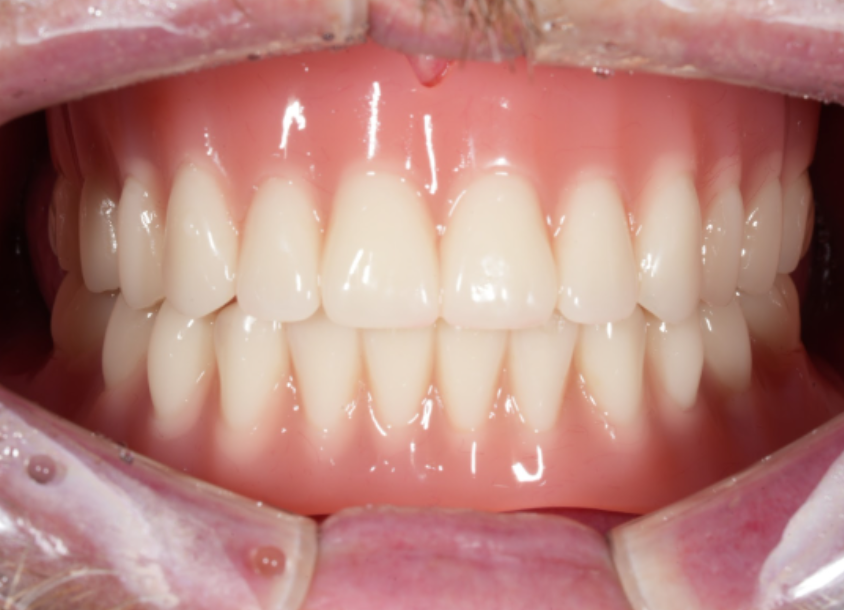

This image shows the completed overdenture in place.

In fully edentulous cases, the implant-supported overdenture structure allows the prosthesis to remain stable and resist movement,

providing significantly improved retention compared with conventional dentures.

Because an overdenture is supported by a locator system connected to implants,

it provides significantly better retention than conventional full dentures that rely solely on the gums.

This structure helps reduce movement during everyday chewing and speaking, improving overall function and comfort.

In addition, because the overdenture is removable, oral hygiene is easier to maintain,

and components such as retention caps can be replaced or the internal surface adjusted during regular check-ups.

For fully edentulous patients, the stability of the prosthesis often plays a crucial role in food choices, confidence, and social activities.